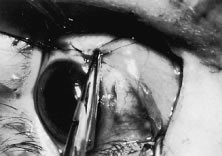

A no. 15 surgical knife or other similar instrument is used to penetrate the conjunctiva at the limbus (Fig. 50). Care is taken to approach the limbustangential to the globe so that inadvertent penetration of the sclera or cornea is avoided. A Westcott scissors also may be used to incise the conjunctiva at the limbus. To facilitate this step, conjunctiva is lifted gently with a 0.5-mm Castroviejo forceps (see Fig. 50).

Fig. 50. The surgeon is tenting the conjunctiva at the limbus. A blade is used to penetrate the tissue at the limbus.

A blunt-tipped Westcott scissors is used to extend the incision for about 3 clock hours (Fig. 51). Once the fused area of conjunctiva and anterior Tenon's capsule has been penetrated, blunt dissection is performed to carry the limbal incision back toward the muscle. This maneuver is best accomplished by directing the closed tips of a blunt-tipped Westcott scissors into the tissue and letting them open to spread the tissue in a plane between the scleral surface and the underside of Tenon's tissue. The limbal incision is extended radially with a Westcott scissors (Fig. 52). Care is taken to avoid cutting into the anterior portion of the rectus muscle insertion (Fig. 53).

Fig. 51. A blunt-tipped Westcott scissors is used to expand the incision just anterior to the rectus muscle.